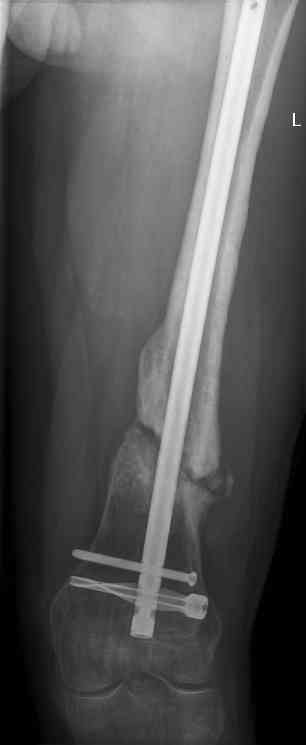

Feb 07

feb 07: retrograde nail + bone graft + BMP